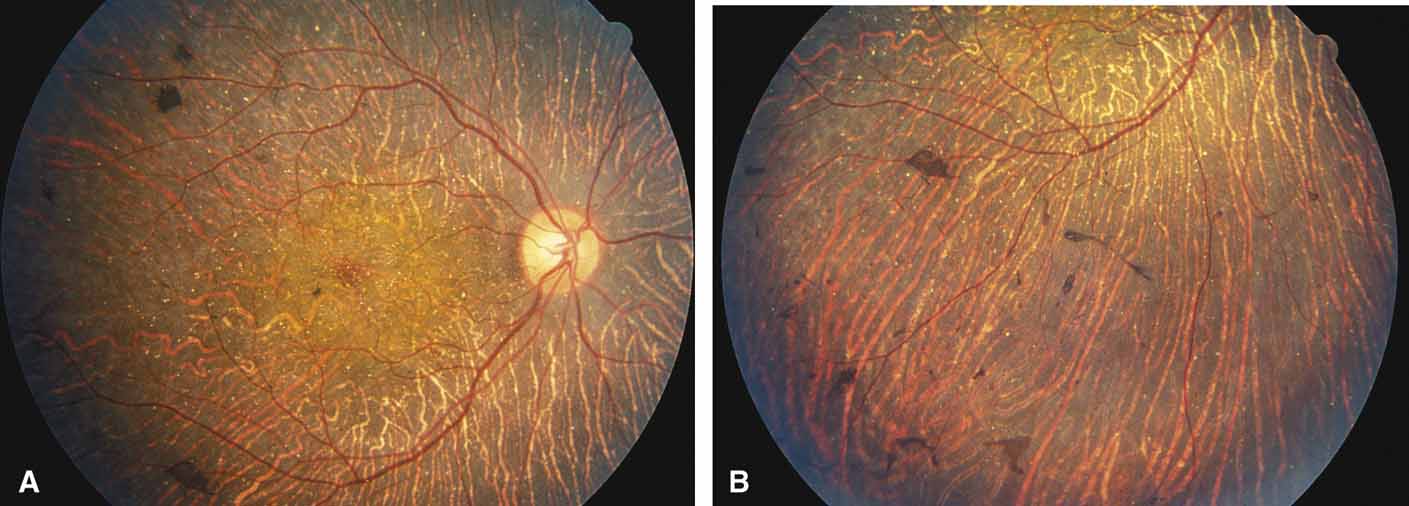

Gyrate atrophy of the choroid and retina with hyperornithinemia from ornithine aminotransferase deficiency. Gyrate atrophy of the choroid and retina (MIM No. 258870) is an autosomal recessive disease that is associated with a 10- to 20-fold elevation of plasma and tissue levels of ornithine.49–52 Vitamin B6 responsive and nonresponsive forms exist. Although the disease is found worldwide, the greatest number of patients, nearly 50% of those reported (all B6 nonresponsive), are of Finnish descent.52 In the first or second decade of life, patients experience night blindness and begin to develop irregular round areas of total vascular choroidal atrophy (Fig. 10A).50 These lesions enlarge and coalesce with time, forming extensive atrophy in the periphery that is associated with constriction of the peripheral visual field (Figs. 10B and 10C). The classic appearance of the fundus is that of a sharp transition from more normal retina to nearly complete atrophy of the choroid and retina (Figs. 11A and 11B).50,53 Central vision may be lost from cystoid macular edema, epiretinal proliferation, or macular involvement in the atrophic process (Figs. 11C and 11D).50 Many patients will develop clinically significant posterior subcapsular cataracts. The ERG and EOG are markedly abnormal from early in the course of the disease.54